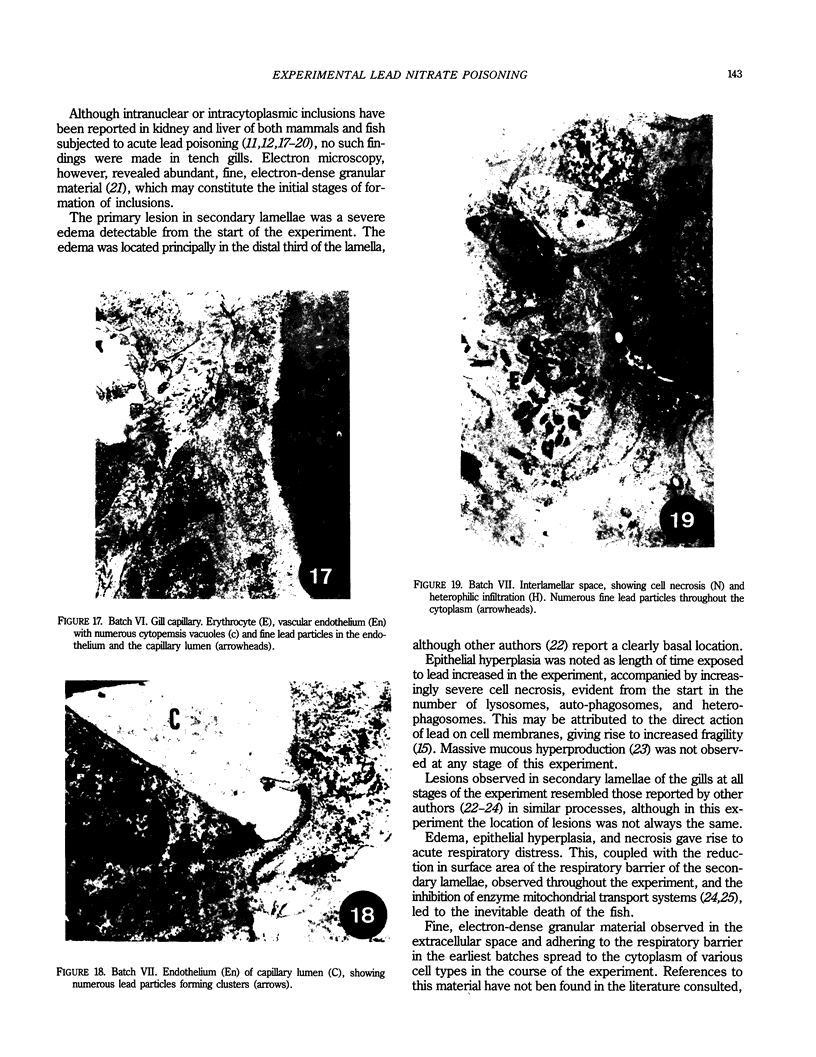

A microscopic, ultrastructural, and morphometric study was made of the gills of tench (Tinca tinca, L.) subjected to acute experimental lead nitrate poisoning. Twenty-one adult tench were subjected to poisoning and a further 22 were used as controls. Lesions were characterized by the appearance of edema and epithelial hyperplasia and necrosis, both in cells forming part of the filtration barrier and in those in the interlamellar space. These processes developed in the course of the experiment, leading to the death of tench after 12 to 15 days of exposure to 75 ppm lead nitrate, at which point the concentrations of lead in the gills had reached their maximum.